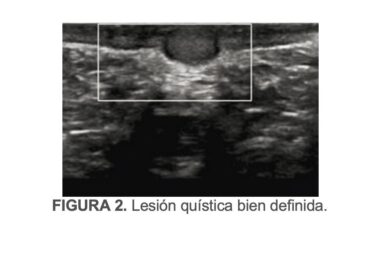

Al examen físico, se identifican las lesiones ya comentadas, sin orientación diagnóstica definitiva; motivo por el cual se solicitó ultrasonido del área afectada.

Se reporta testes, epidídimos, plexos pampiniformes, túnica y bolsa escrotal de carácteristicas normales, acompañadas de lesiones cutáneas de apariencia quística no fijas a planos profundos (FIGURA 2).